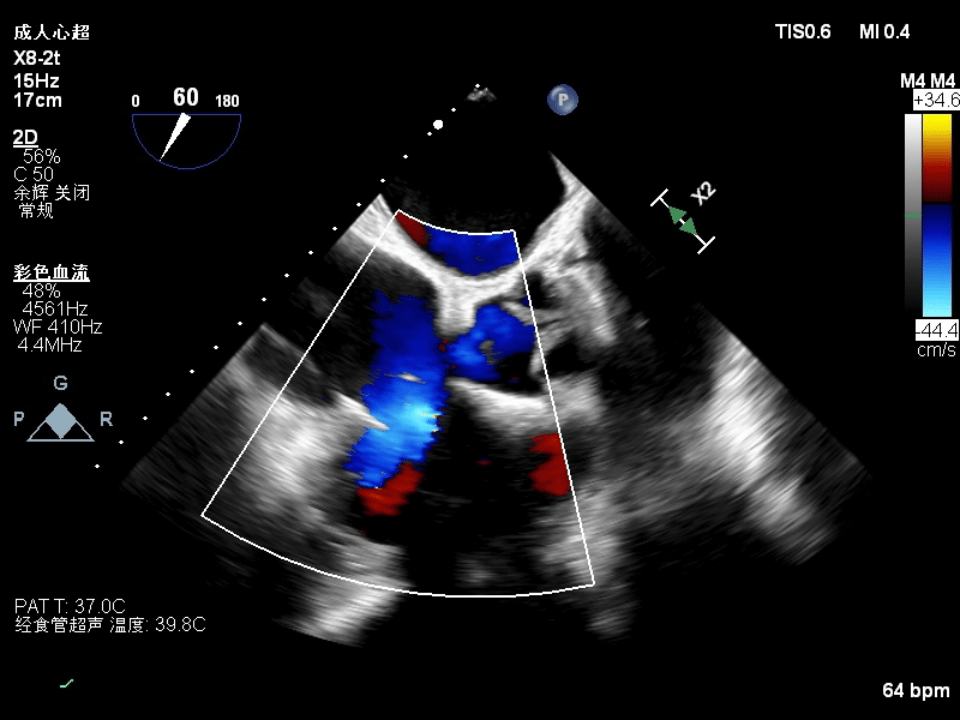

Following right coronary artery protection, the procedure was performed using a large sheath under the guidance of ultrasound and DSA. A 14T K-Clip® was implanted at the junction of the posterior and septal leaflets of the tricuspid valve. Due to factors such as the pacemaker lead and cardiac rotation, the process was somewhat challenging. Guided by TEE, the anchor screw was advanced into the appropriate hinge region, and after clamping, satisfactory results were achieved, with reduced annular area and circumference and significant improvement in regurgitation. Subsequently, a second 14T K-Clip® was implanted at the junction of the anterior and posterior leaflets. The regurgitation severity decreased from grade 5+ preoperatively to grade 2+, with notable improvement in leaflet coaptation. The overall outcome met expectations, and the procedure was successfully concluded.

Preoperative TR: 5+ Postoperative TR: 2+